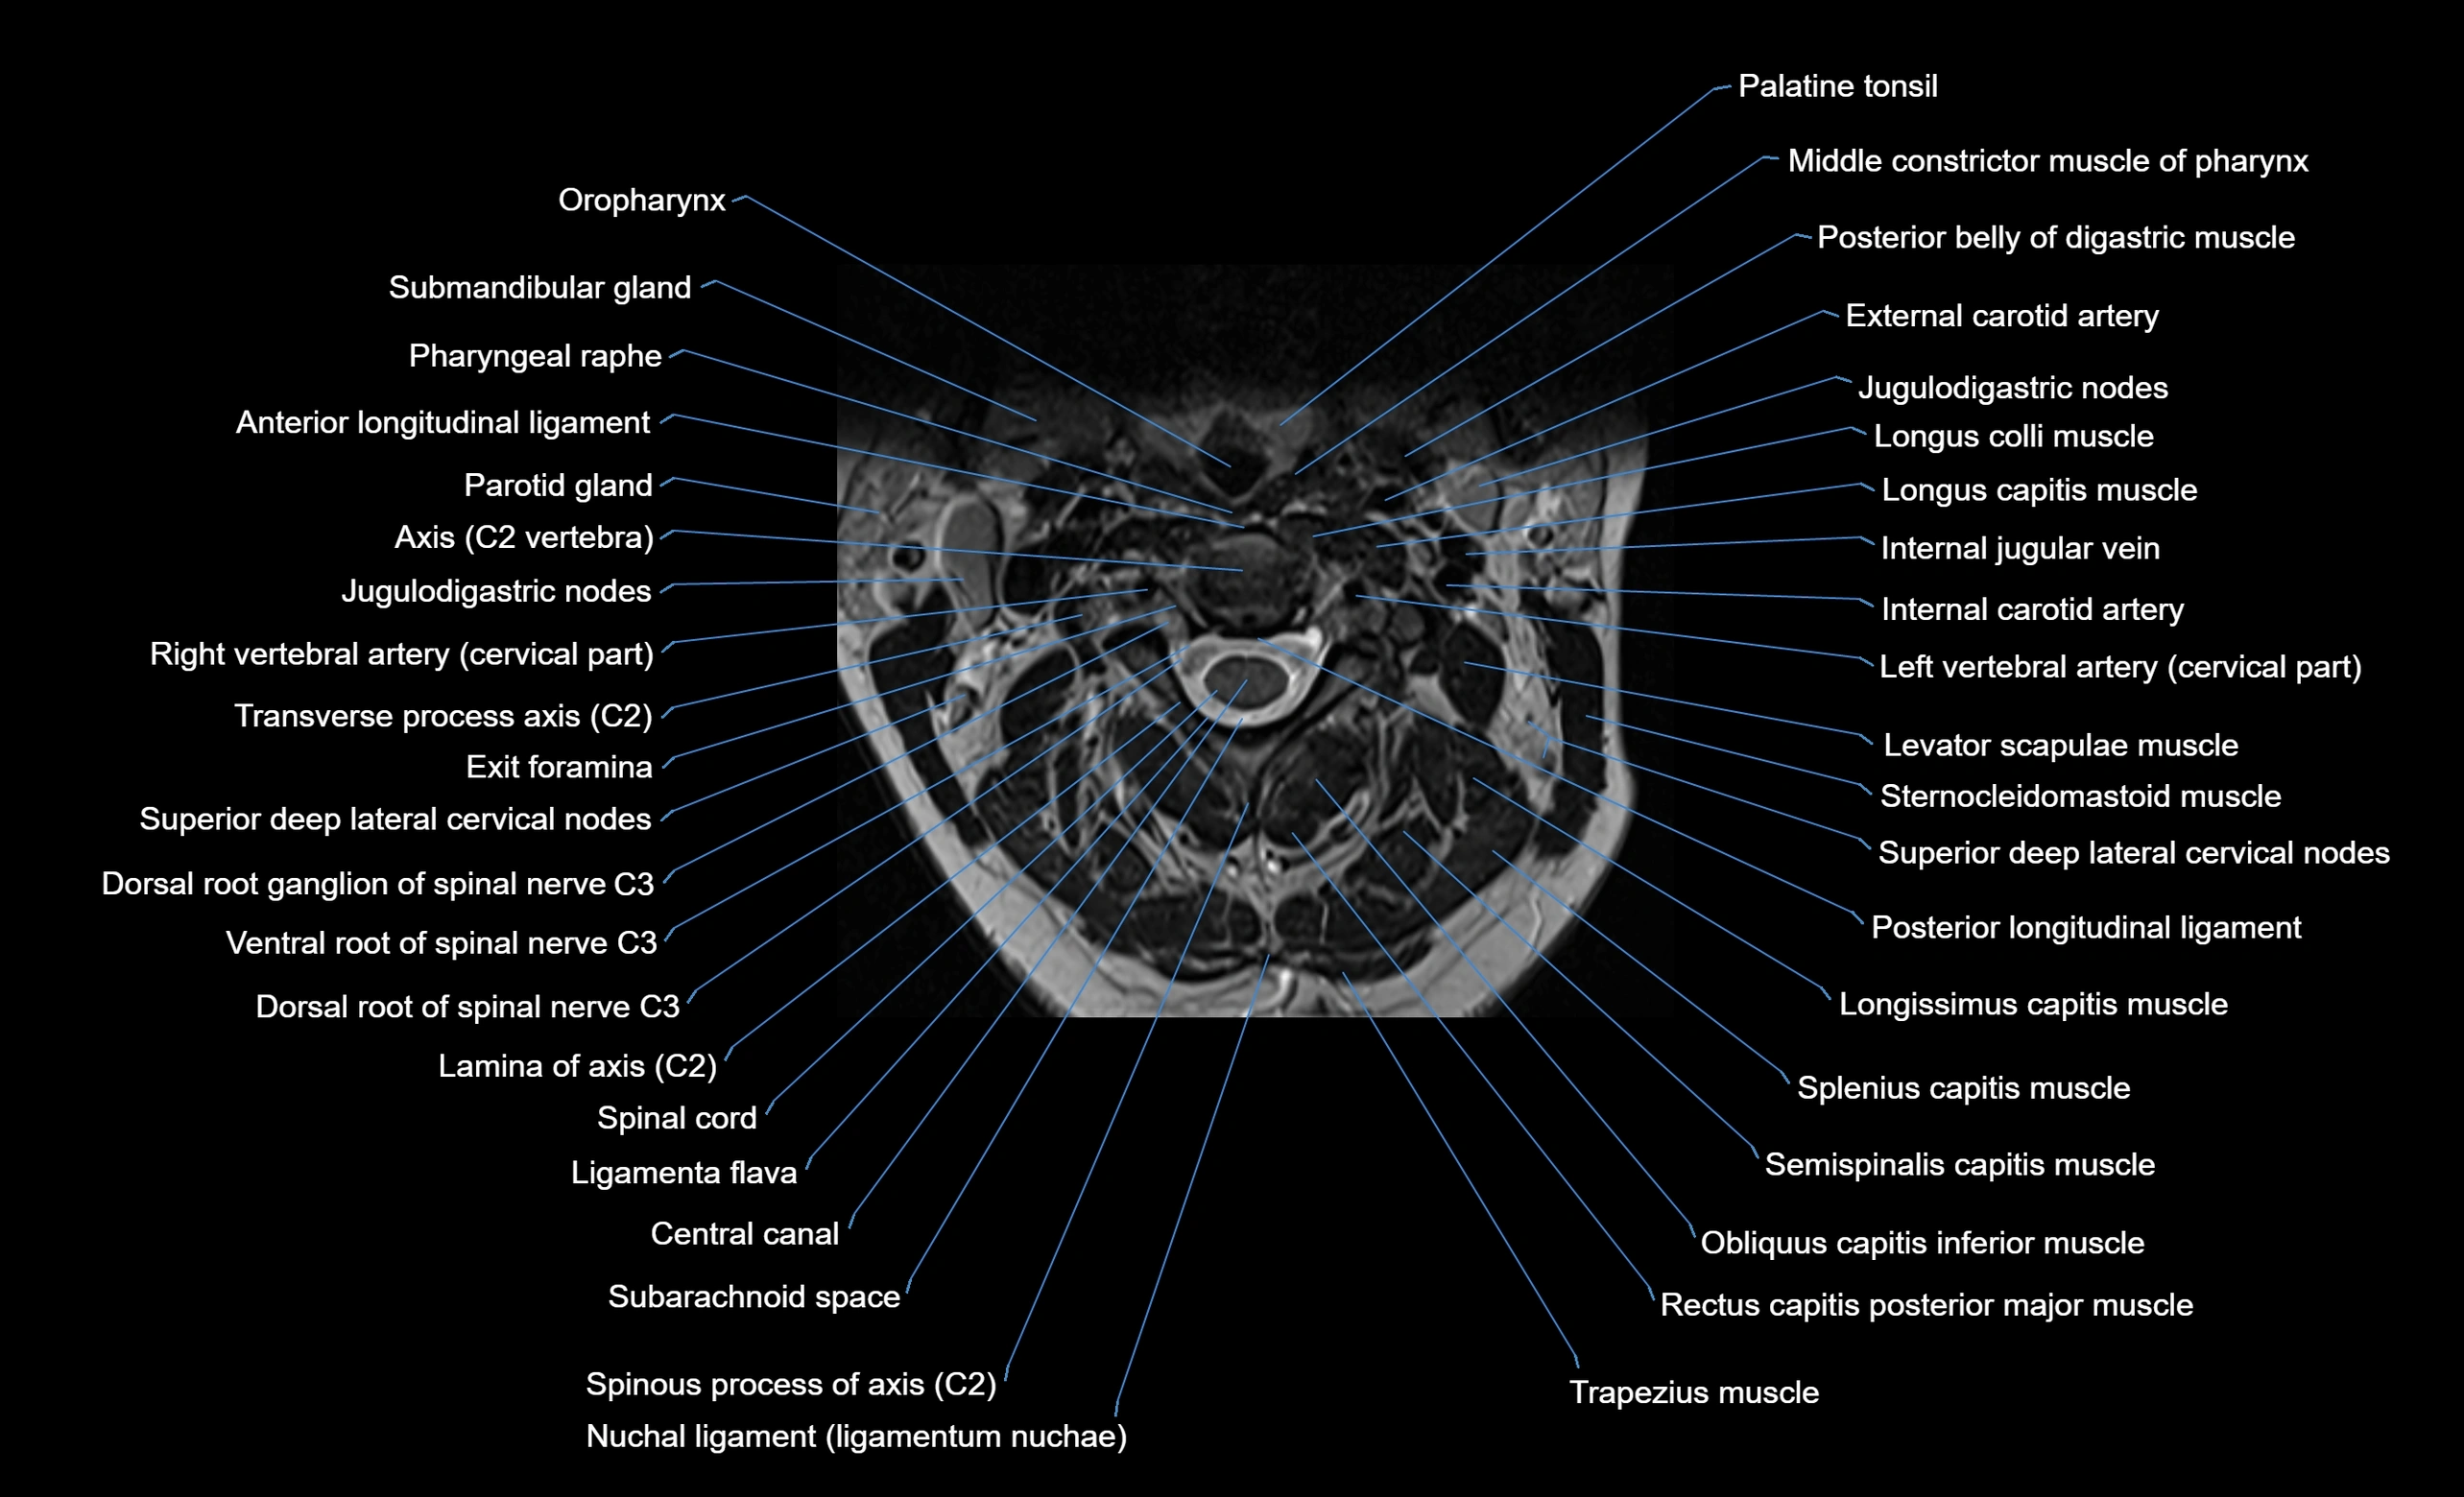

MRI image

image